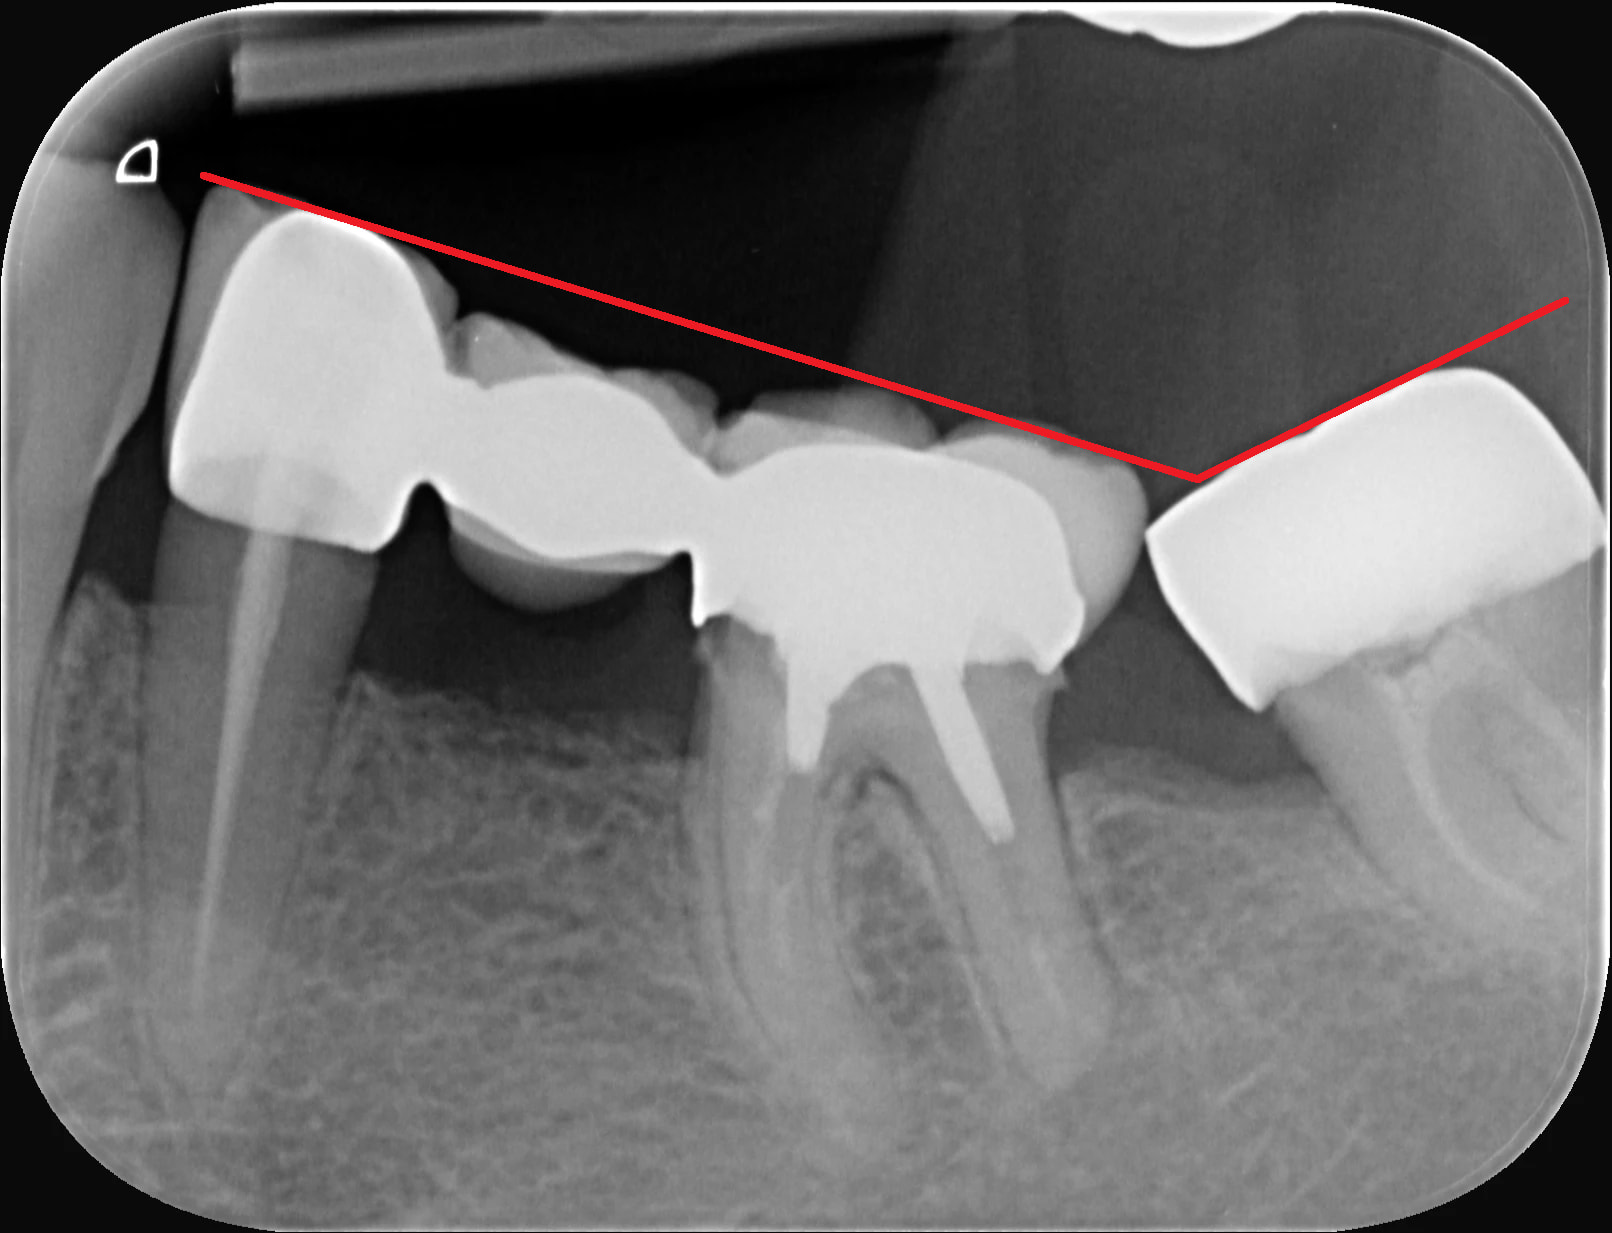

Je pensais faire le retraitement endo (j'ai déposé la couronne et l'ancrage , pas de fracture à la dépose.)

A la vue de la radio, retraitement, surtout si tu as déposé l'inlaycore. Il va faire un implant en 36 et la 35?

Quel âge a la patiente. Le retraitement est faisable, l'implant permettrai de mieux gérer l'espace avec la 38 puisqu'il semble manquer la 37 et que l'on a une mesialisation de la 38.

Probablement une lésion sur la racine distale, visible sur la pano, possiblement avec des épisodes d'abcès apical aiguë.

Si j'étais mauvaise langue, je dirais qu'elle génait la pose d'un implant en position de 36.

S'il faut chercher une raison acceptable de l'avulser sans avoir vu la dent, je pense qu'on peut argumenter la finesse au niveau de la jonction plancher/racine qui pourrait faire craindre une fracture.

Étant endo / implanto je peux dire que ce cas est clairement très favorable pour un retraitement.

Lésion distale en raison d’une obturation ancienne dont on voit la perméabilité sur la rétro alvéolaire.